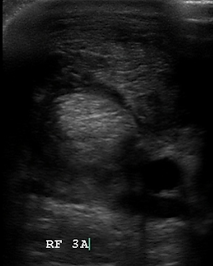

The scan showed severe disruption of fibre pattern, loss of tendon echogenicity and swelling.

The scan revealed significant swelling and marked oedema within the tendon, along with severe disruption of the fibre pattern.

Improved scan images, granulation tissue filling in the tendon, still disrupted longitudinal fibre pattern, still prominent enlargement of the tendon

Excellent progress on the scan, granulation tissue completely filled up the lesion, and a greatly improved longitudinal fibre pattern is present.